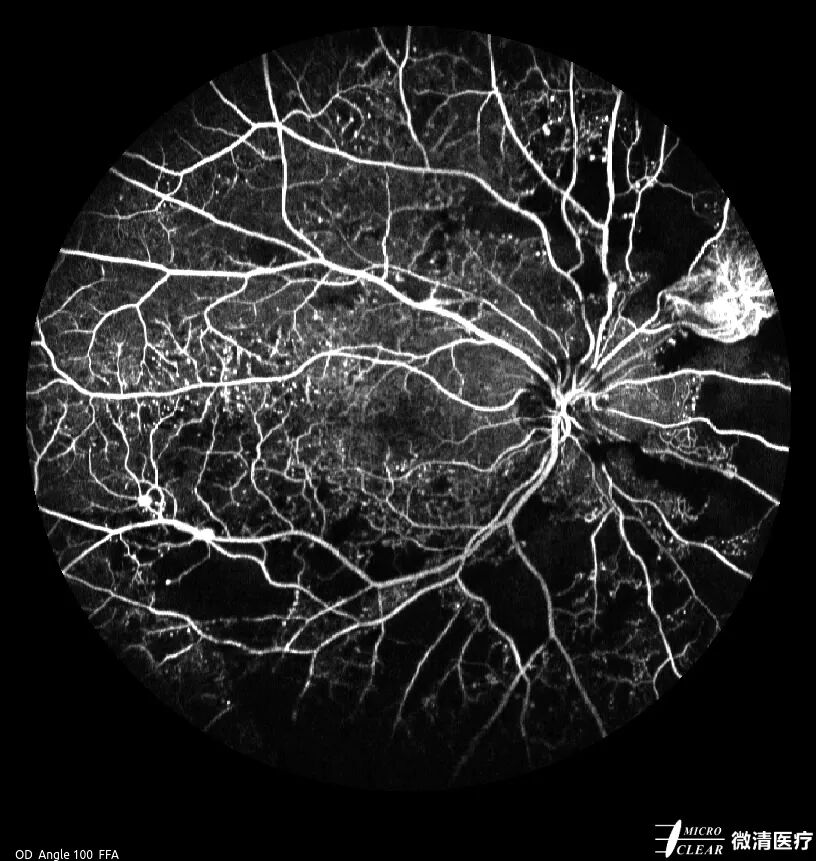

充盈异常:包括充盈缺损、充盈迟缓、逆行充盈,常见于糖尿病性视网膜病变(无灌注区)、视网膜中央动脉阻塞、视网膜静脉阻塞等。

糖尿病性视网膜病变无灌注区(左)、视网膜中央动脉阻塞(右)